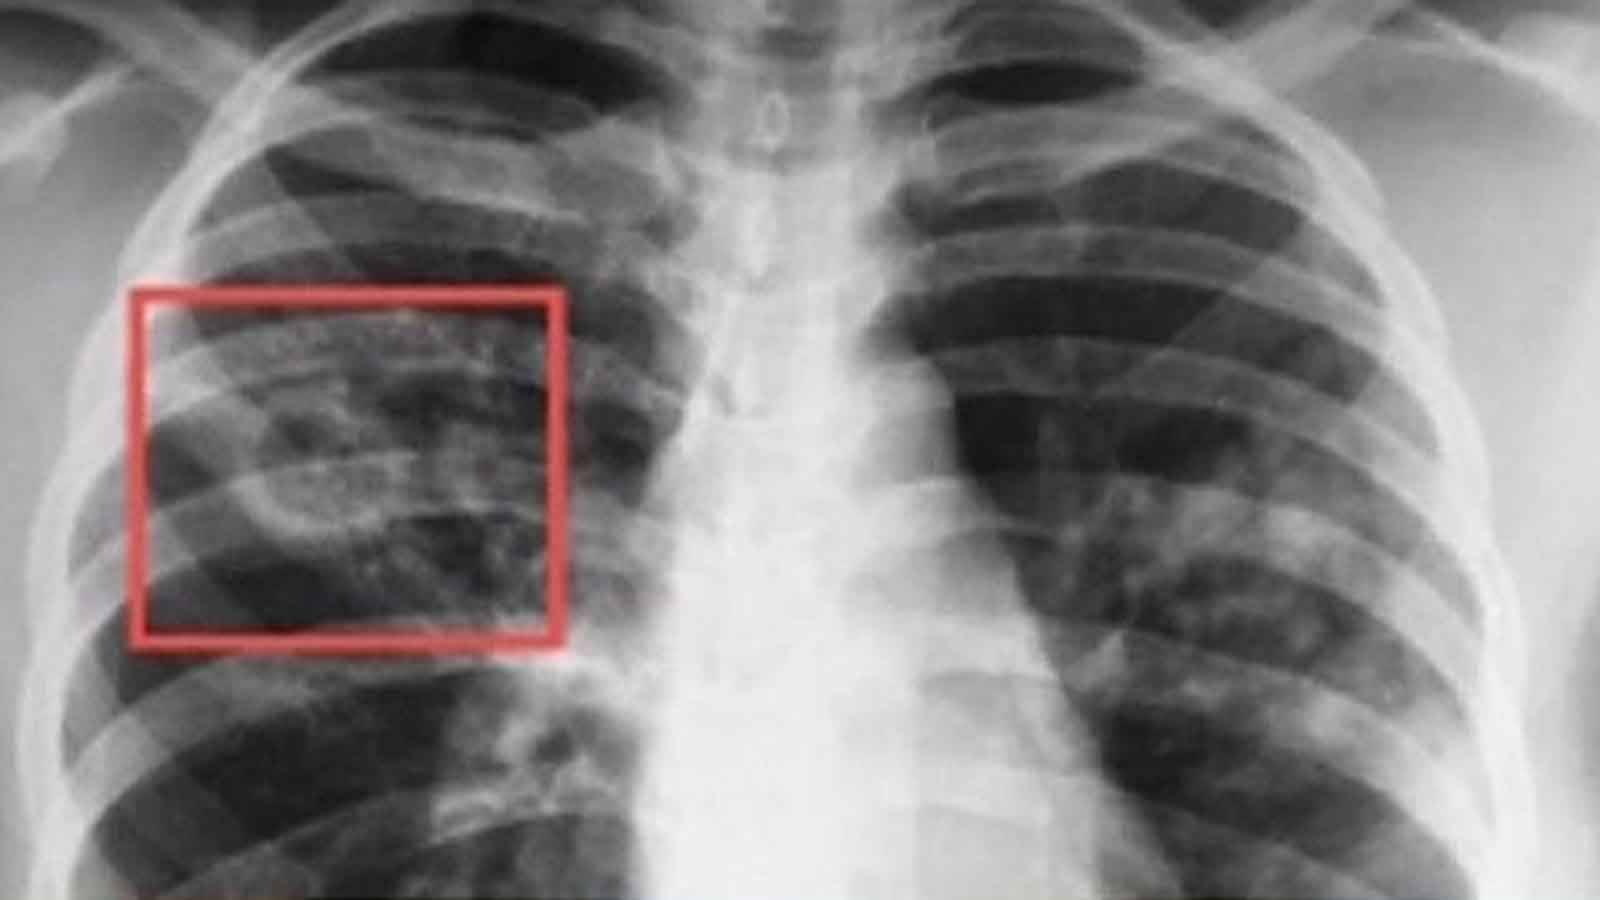

- рентгенография покажет, что инфильтраты локализуются преимущественно в верхних отделах, от них отходит дорожка к корню легкого;

Расположение очаговых теней (очагов) на снимке (теней размером до 1 см) в верхних отделах легких, наличие кальцинатов (теней округлой формы, по плотности сравнимых с костной тканью) типично для туберкулеза. Если кальцинатов множество, то вероятно, что у человека был довольно близкий контакт с больным туберкулезом, но заболевание не развилось. Признаки фиброза, плевроапикальные наслоения на снимке могут говорить о перенесенном туберкулезе.

- Рентгенография легких: инфильтраты чаще локализуются в 1, 2 и 6 сегментах легкого. От них к корню легкого идет так называемая дорожка, которая является следствием перибронхиальных и периваскулярных воспалительных изменений.

Пациенту проводят рентген легких в 2 проекциях. При свежем заболевании на снимке очаги представлены в виде теневых образований небольшого и крупного размера, имеющих округлую форму. Нередко они локализуются в верхних отделах легких. Для хронической формы патологии характерны плотные фокусы с очагами фиброзных тяжей. При фиброзе ткани легкого мелкие очаги соединяются и перемещаются к верхушке легкого, а к плевре тянутся тени в виде полос.